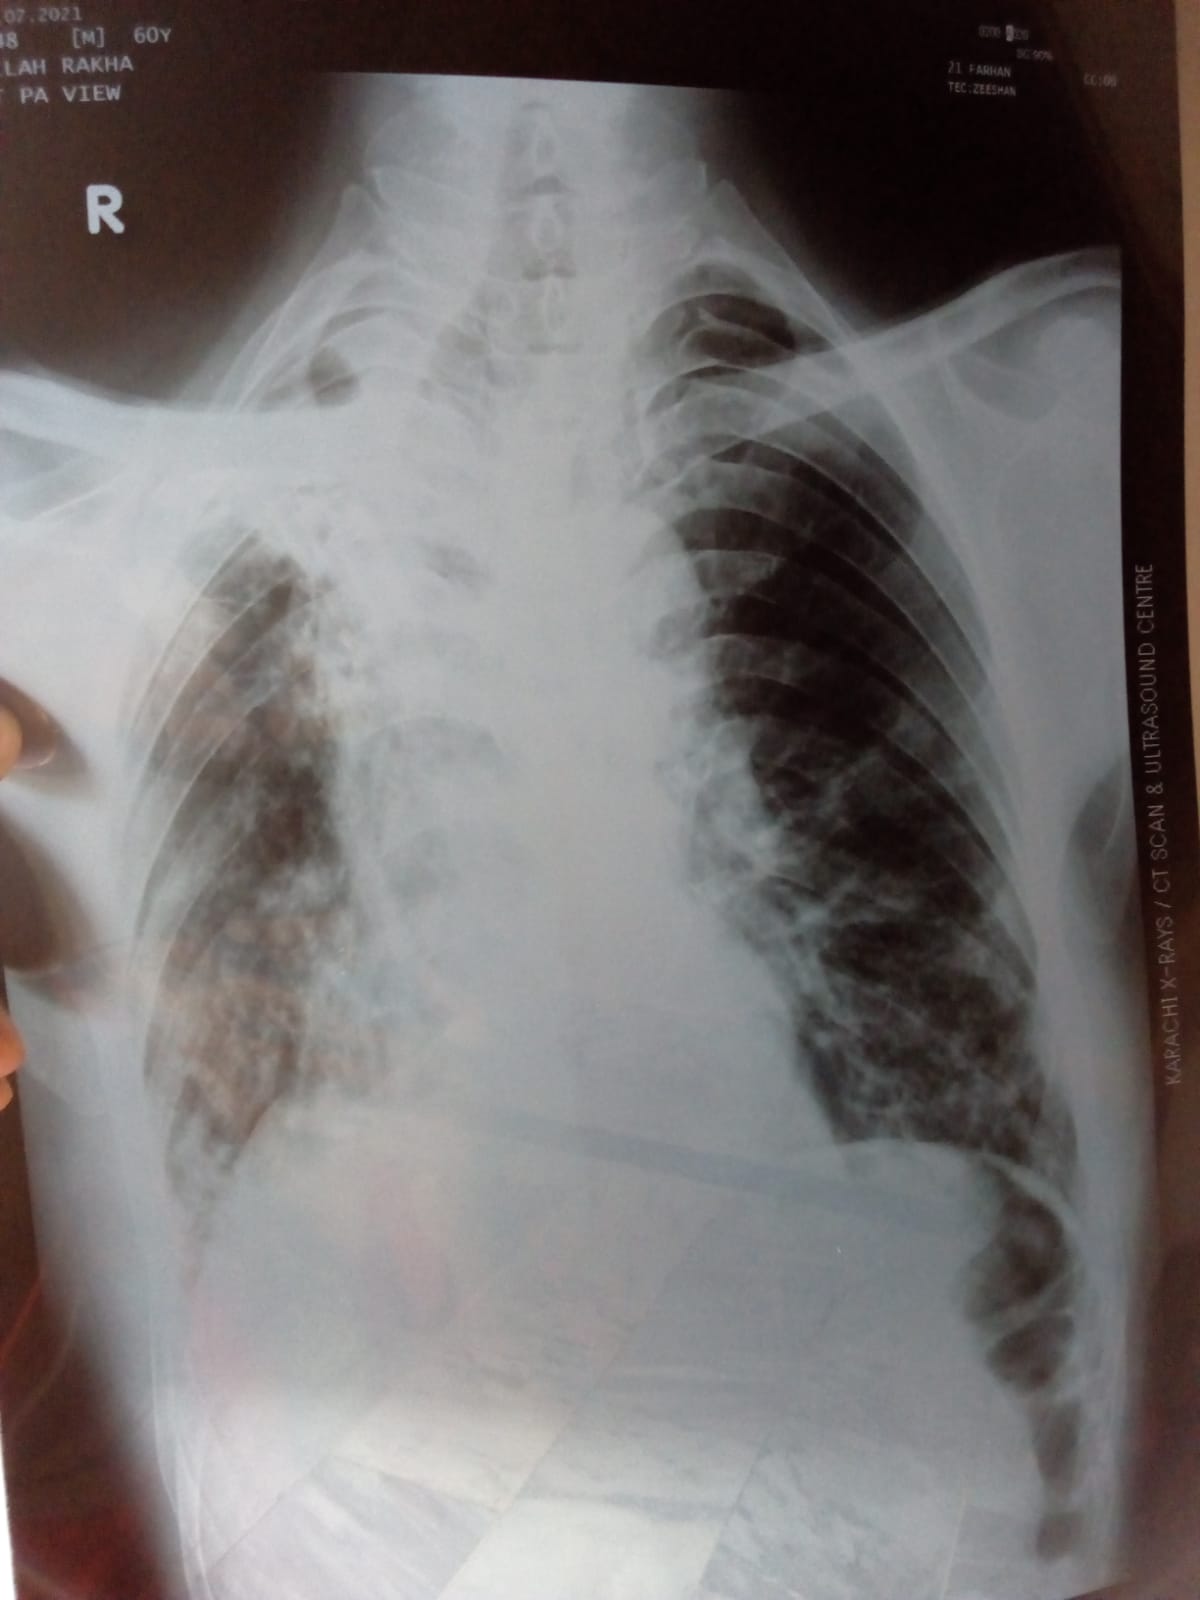

Asking for Father, Male, 60 years old, Karachi

Mere father ko kuch dino s bht zyada khansi h or bht kamzoor horhe h. Chest xray krwaya h, pls dr bata dijeye kya likha hai khair..

its very serious. take him to a hospital

old healed koch bronchiaiatic changes